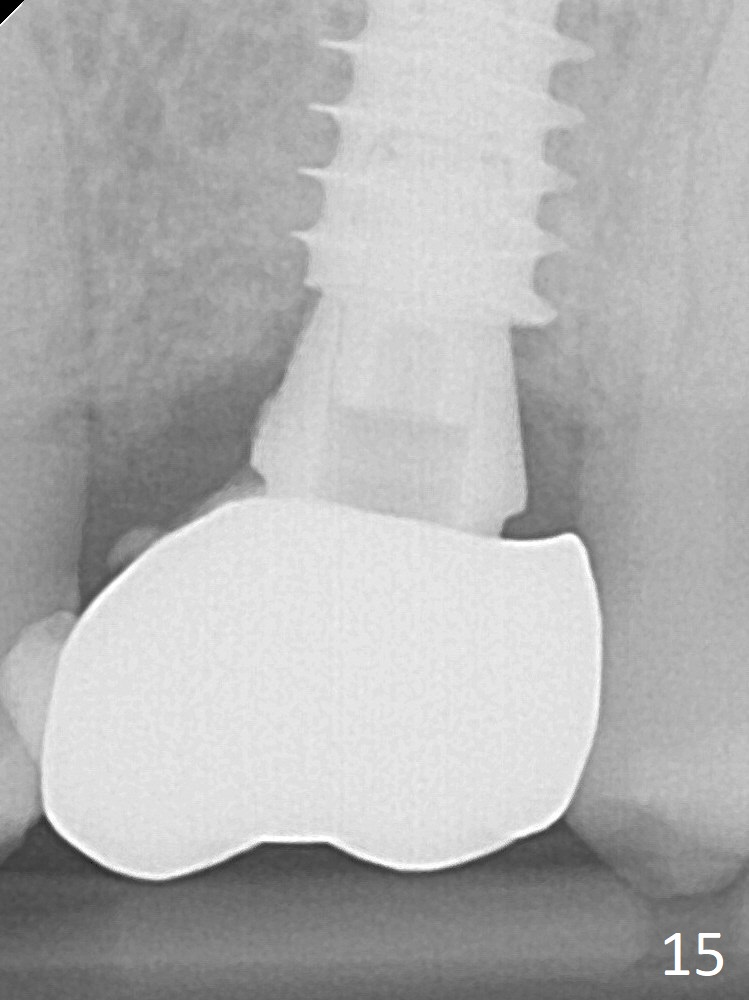

The crown dislodges 8 months post cementation, probably due to bruxism, small, short abutment and open margin (Fig.15 (taken after recementation; the residual cement is removed later)).